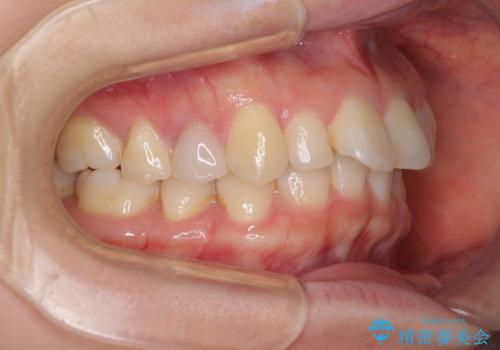

下顎前歯2本が先天欠損しており、上顎歯列に対して、下顎歯列がアンバランスに小さい状況でした。

左右上顎側切歯2本が矮小歯であるため、上顎の抜歯ではなく、IPR(歯と歯の間を削る)と歯列全体の後方移動によってバランスを整えることとしました。

歯列のバランスが悪く、インビザライン矯正特有の奥歯の噛みにくさがなかなか改善されず、治療期間が長期化してしまいました。